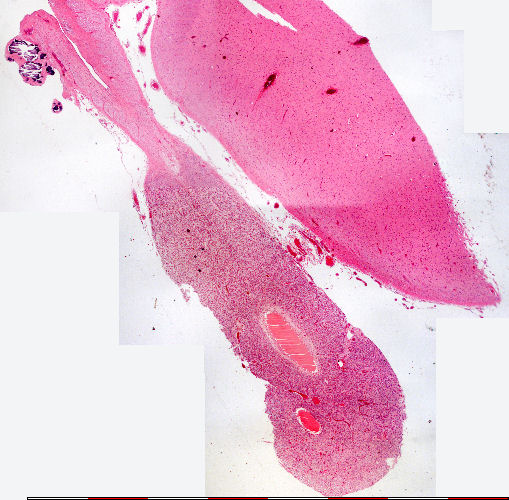

Pineal gland: Very low magnification

Pineaal liggaam/ Pineal body

Brein / Brain

Steeltjie / Stalk

Pia mater

Bindweefsel / Connective tissue